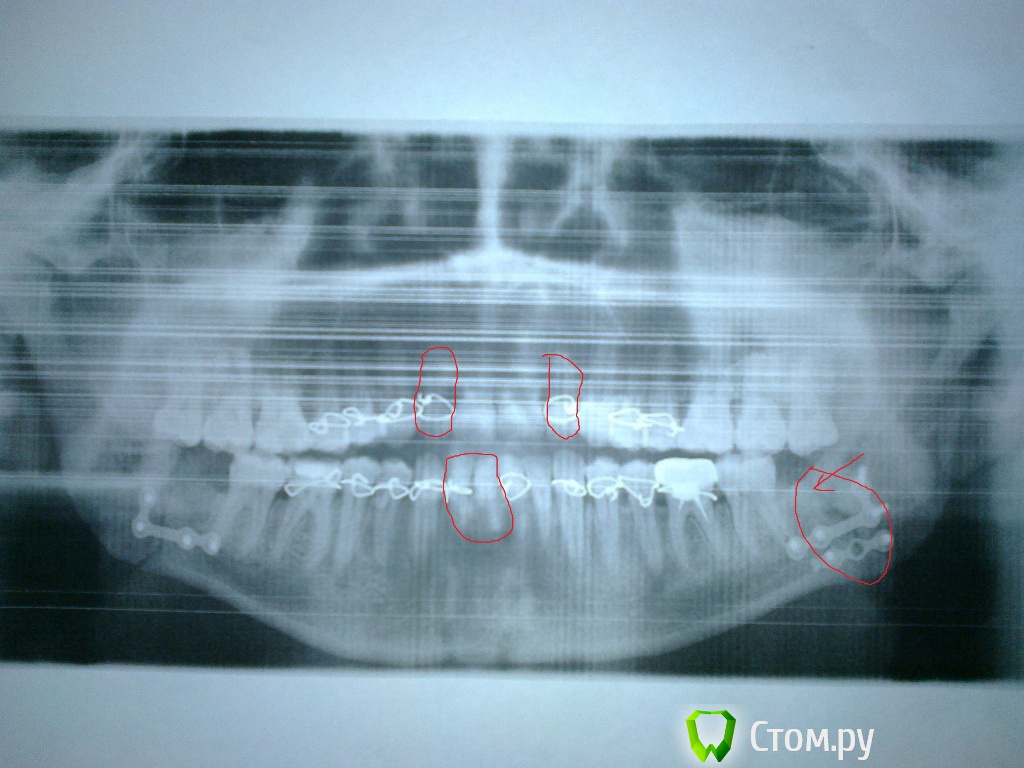

ivanich 82 Опубликовано 1 июля, 2014 Автор Поделиться Опубликовано 1 июля, 2014 Уважаемые форумчане, был сегодня на приеме в ЧЛХ Окружной больницы г. Сургута ХМАО-Югра, сделали еще снимок, сказали операция проведена правильно, но так как стоматолог-хирург снял мне резиновые тяги очень рано и заставил разрабатывать челюсть, произошла небольшая трещина в месте перелома (данное место отмечено стрелочкой), связали впереди челюсть вновь резиновыми тягами и сказали так ходить еще месяц. Но зубы передние не совпадают, получается все равно как буд-то нижняя челюсть выехала вперед, сейчас зубы впереди болят, хотя и не соприкасаются. Беспокоят зубы, которые я отметил красным, сверху они расшатались очень, а снизу почему-то настолько оголились корни, что мне стало страшно. Почти неделю полоскал "Стоматофитом" и пил "Кальцемин". Подскажите, что все таки произошло с зубами или прикусом? Как сохранить зубы, чтобы после дай бог снятия, тяг, не выпали зубы. Начинает нападать деприсняк(((((((((((( Ссылка на комментарий

АнтонТЛТ Опубликовано 2 июля, 2014 Поделиться Опубликовано 2 июля, 2014 Отломки сопоставлены удовлетворительно. На счет передних зубов, хорошо бы еще лигатуры на центральные резцы.Мы в случае лечения сложных переломов шинами использовали резиновые проставки на зубах, которые контактируют раньше остальных. Можете сделать нормальное фото нижних зубов? 1 Ссылка на комментарий